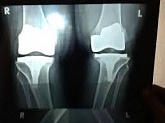

Endoprothetik des Kniegelenks

In den späten Stadien der Arthrose des Knies durch eine ausgeprägte Begrenzung der Bewegung begleitet, konstant starke Schmerzen, körperliche Unversehrtheit Verformung bis zur Genesung der einzige Weg ist der Ersatz des betroffenen Gelenks für eine künstliche - Endoprothetik.

Diese Methode ermöglicht es Ihnen, die richtige Form des Gliedes, eine vollständige Palette von Bewegung im Gelenke, zu entlasten ständige Schmerzen und Knirschen bei Bewegung und als Ergebnis wieder herzustellen, signifikant dem Patienten Lebensqualität zu verbessern.

Im Folgenden sind Röntgenaufnahmen und Fotografien, die die Strecke der Bewegung in der betroffenen Gelenke vor und nach der Operation veranschaulichen.